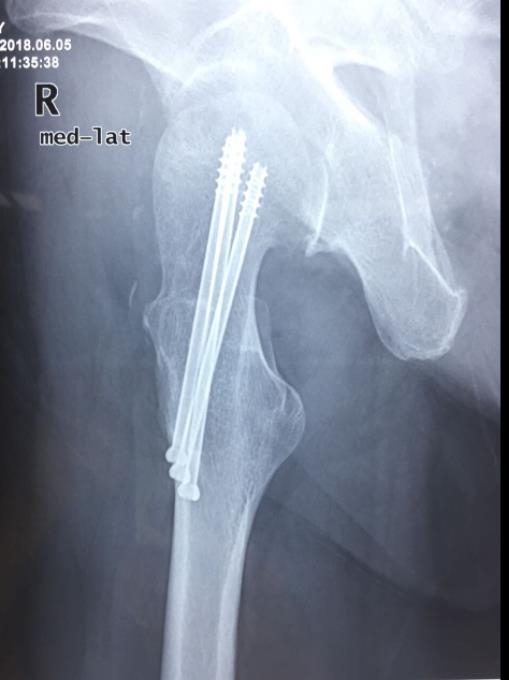

临床病例